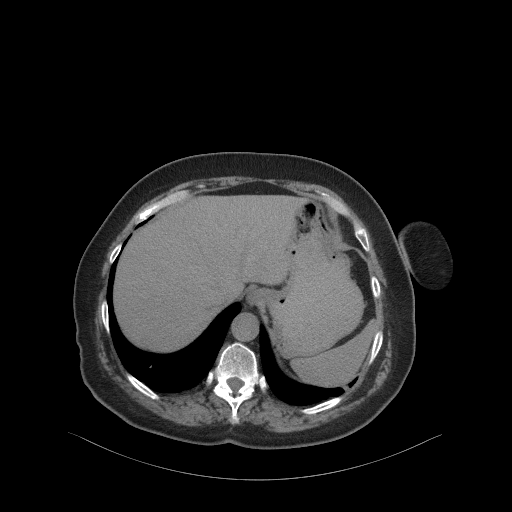

Generated VENOUS CT scan (A→B translation)

Full window (WL 1023.5, WW 4095 β†’ Low βˆ’1024, High +3071)

Actual HU range: [-242.2, 411.7]

Lung window (WL -600, WW 1500 β†’ Low βˆ’1350, High +150)

Actual HU range: [-242.2, 150.0]

Mediastinum window (WL 40, WW 400 β†’ Low βˆ’160, High +240)

Actual HU range: [-160.0, 240.0]